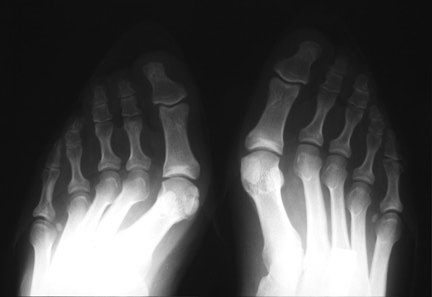

BilatHV:

This patient has a marked hallux valgus deformity in both feet. As the first toe migrates more and more to valgus, it presses against the second toe, and may aggravate dorsal clawing of the second toe, which is usually initiated by overload of the second metatarsal and synovitis of the metatarsophalangeal joint. Also note the relative hyperostosis of the second metatarsal shafts compared to the third and fourth, as well as dorsal rotation of the fibular sesamoids.

HVarus:

This patient has undergone bilateral osteotomy of the medial 1st metatarsal heads (“bunionectomy”). Unlike the Lapidus procedure, this procedure does not correct the underlying splaying of the 1st metatarsal, and can lead to instability of the first metatarsophalangeal joint. In this case, the hallux valgus has been overcorrected, and the patient now has a bilateral hallux varus. Bilateral osteotomies are noted in the 5th metatarsals for correction of “bunionette” deformities.